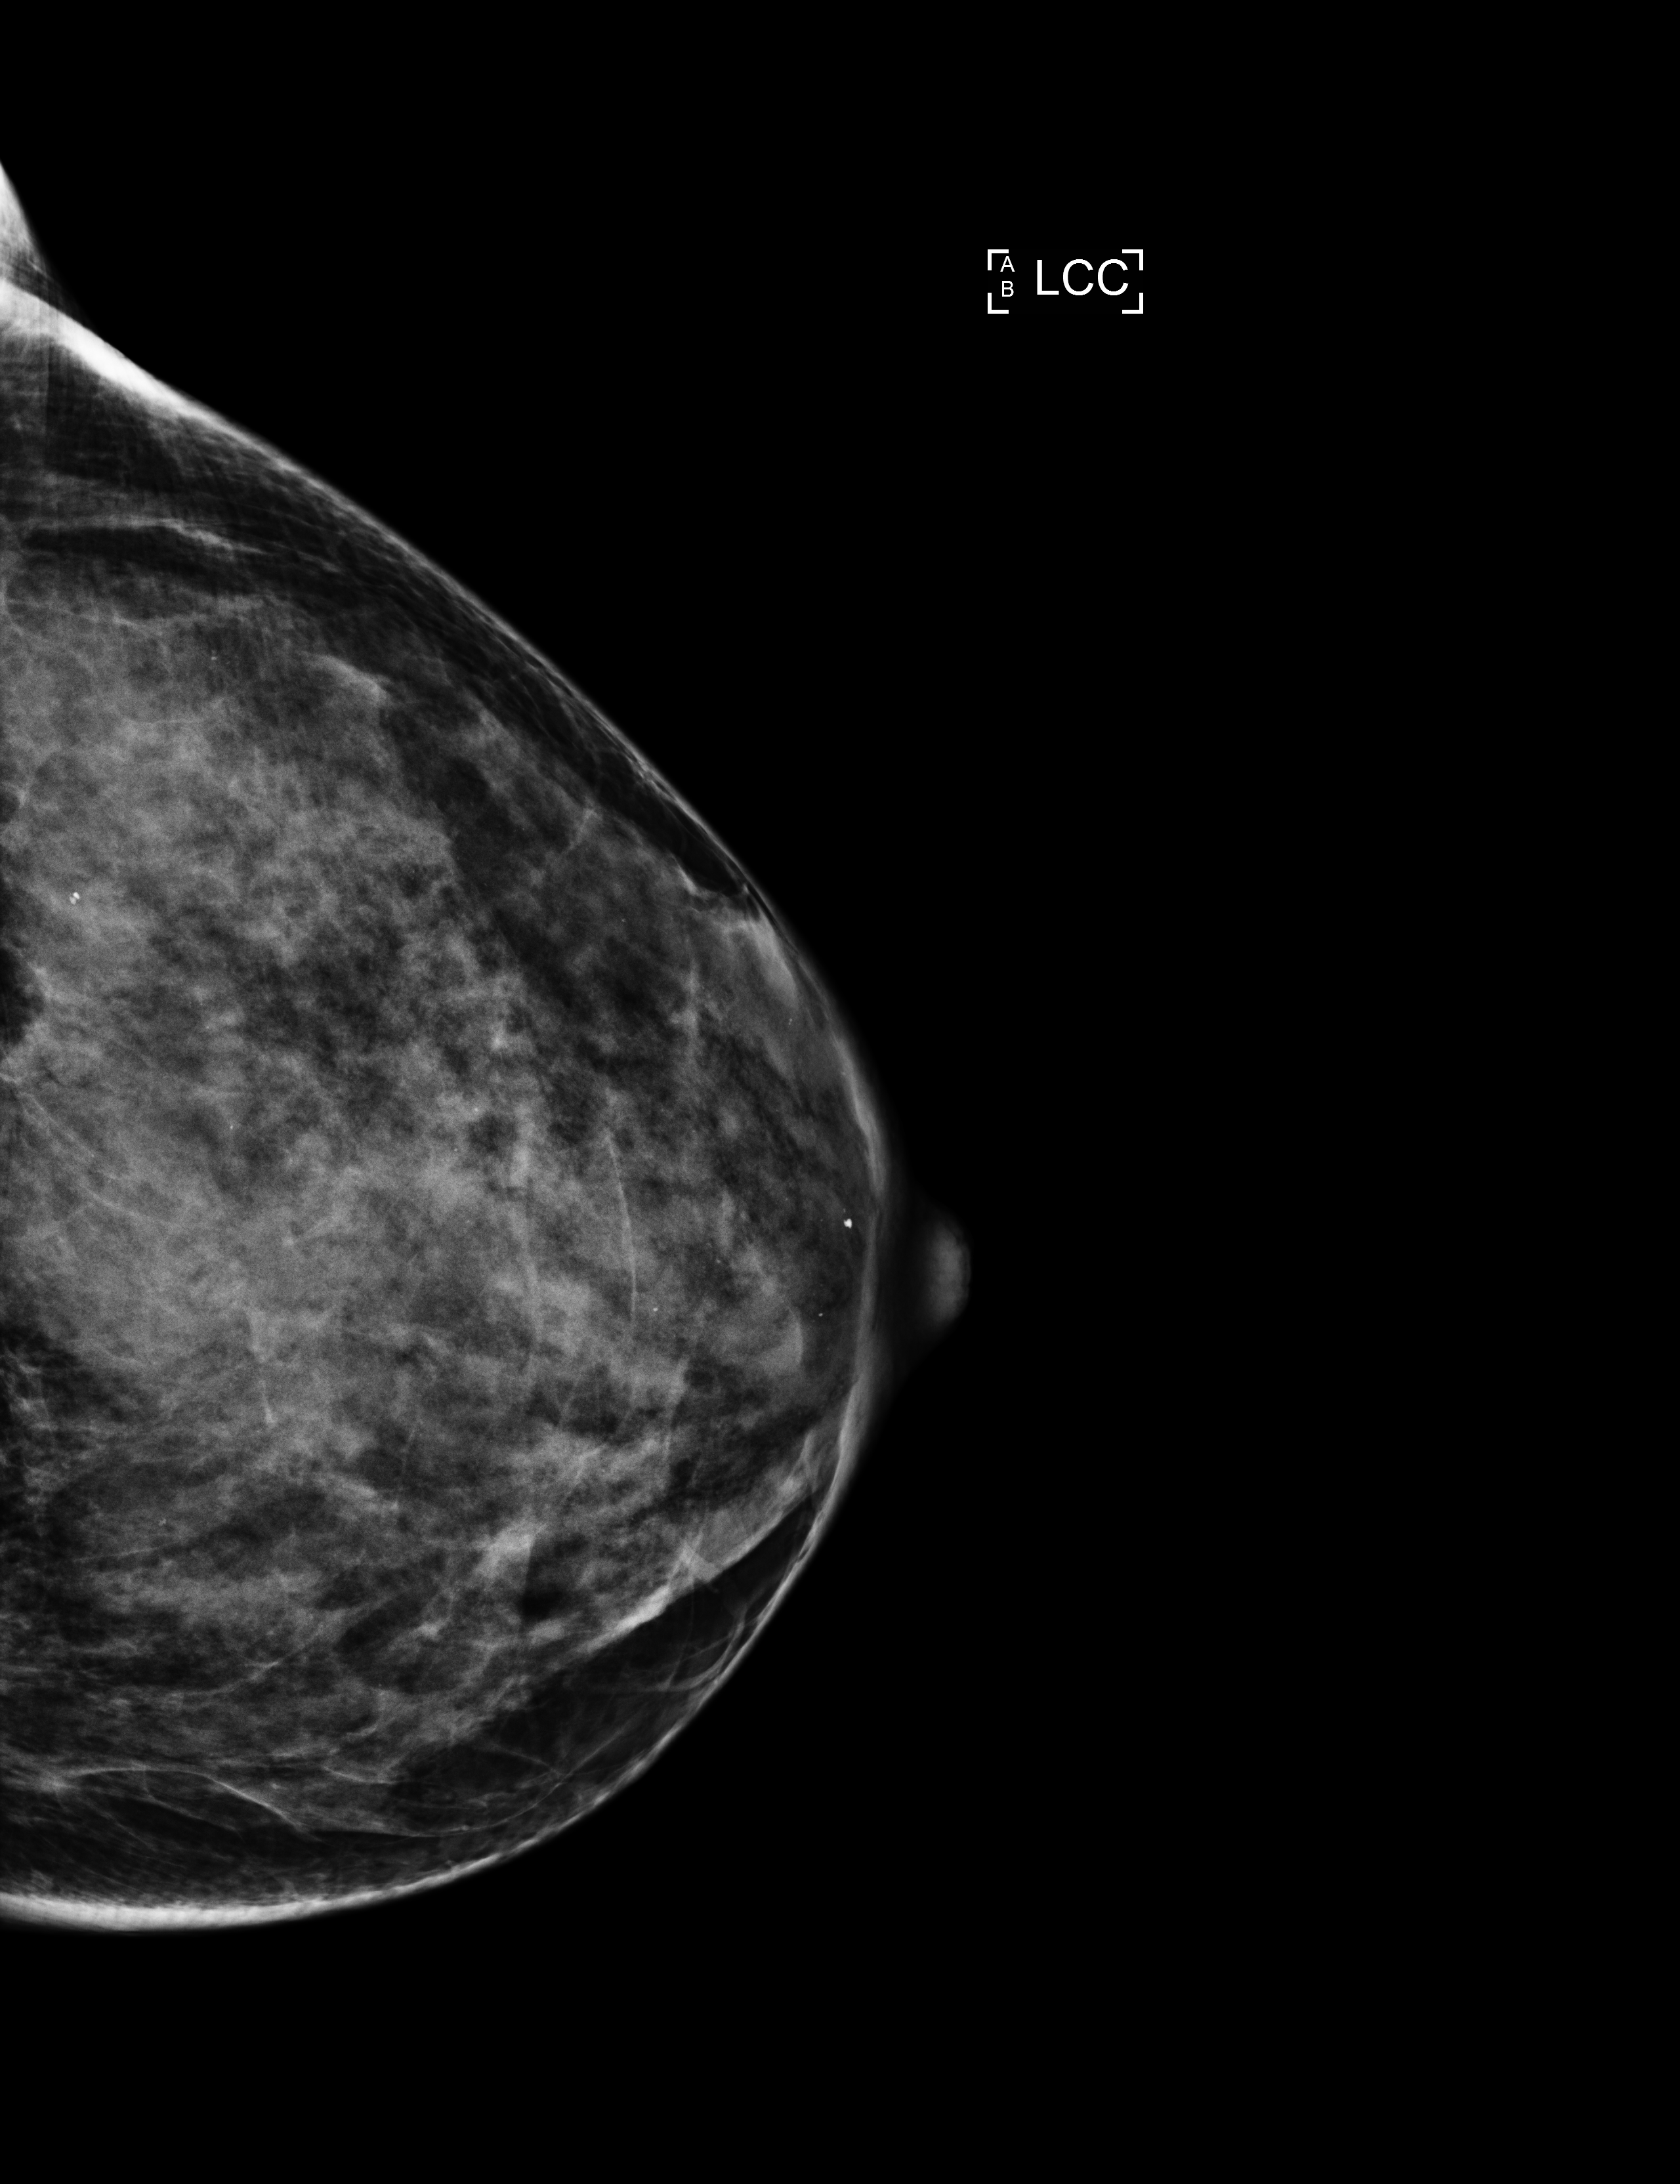

Click on image over the detected lesion. When done click

Save Data

button.

184381_L_CC.png